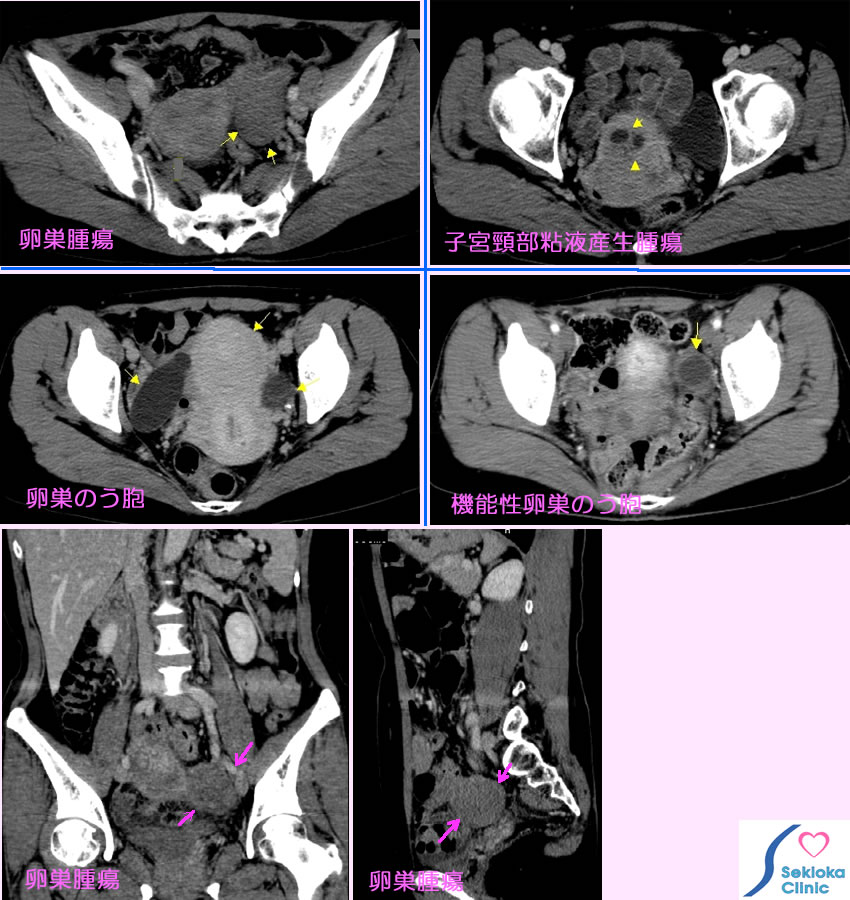

子宮・卵巣腫瘍

下腹部痛、おりものなど。無症状で超音波エコー、CT検査などで見つかることも多くあります。

下腹部痛、腹痛などで超音波エコー、MDCT検査を行ってみつかることが当院ではあります。精査にはMR!、婦人科では経膣超音波エコー、擦過細胞診、生檢なども行われます。

当院では異常が見つかると婦人科に紹介しています。上段左の画像は 卵巣摘出、上段右の画像は 子宮・卵巣摘出。中段左の例は 3ヶ月毎の経過観察となっています。中段右は機能性卵巣のう胞で良性と考えられrます。